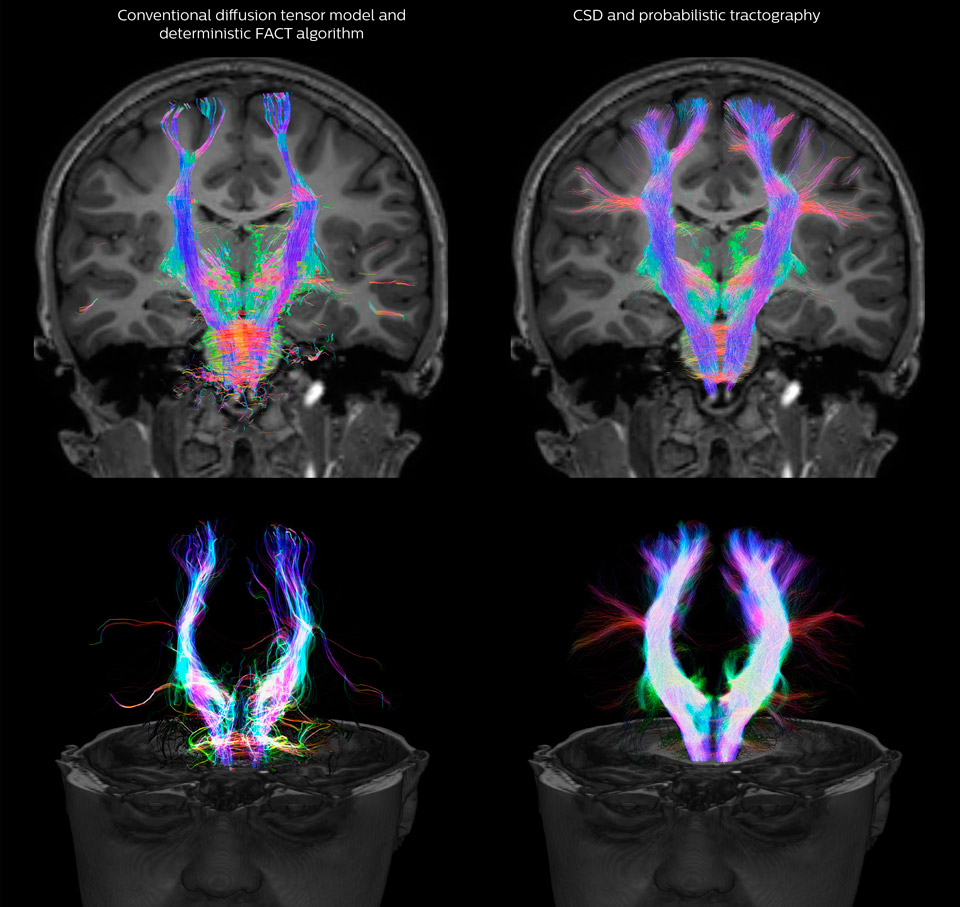

Comparison of fiber tractography methods

Fiber tractography of the corticospinal tract with seed region of the posterior limb of the internal capsule. Different processing based on the same data.

All images were created from the same acquisition in a child using Ingenia 3.0T CX and 32-channel dS Head coil. Diffusion data was acquired at b-values 0, 500, 1000, 2000, 3000. The use of high b-values (3000 s/mm2) effectively suppresses extra-axonal water signal and provides high angular resolution.

Legend of acronyms

CSD: constrained spherical deconvolution

DEC TDI: directionally encoded color track-density imaging

DTI: diffusion tensor imaging

DWI: diffusion-weighted imaging

FOD: fiber orientation density

Data processing was performed using open source software. Fiber tracking was performed using the MRtrix package (J-D Tournier, Brain Research Institute, Melbourne, Australia, https://github.com/MRtrix3/mrtrix3), Tournier et al. 2012. DEC TDI based on F Calamante et al 2010.